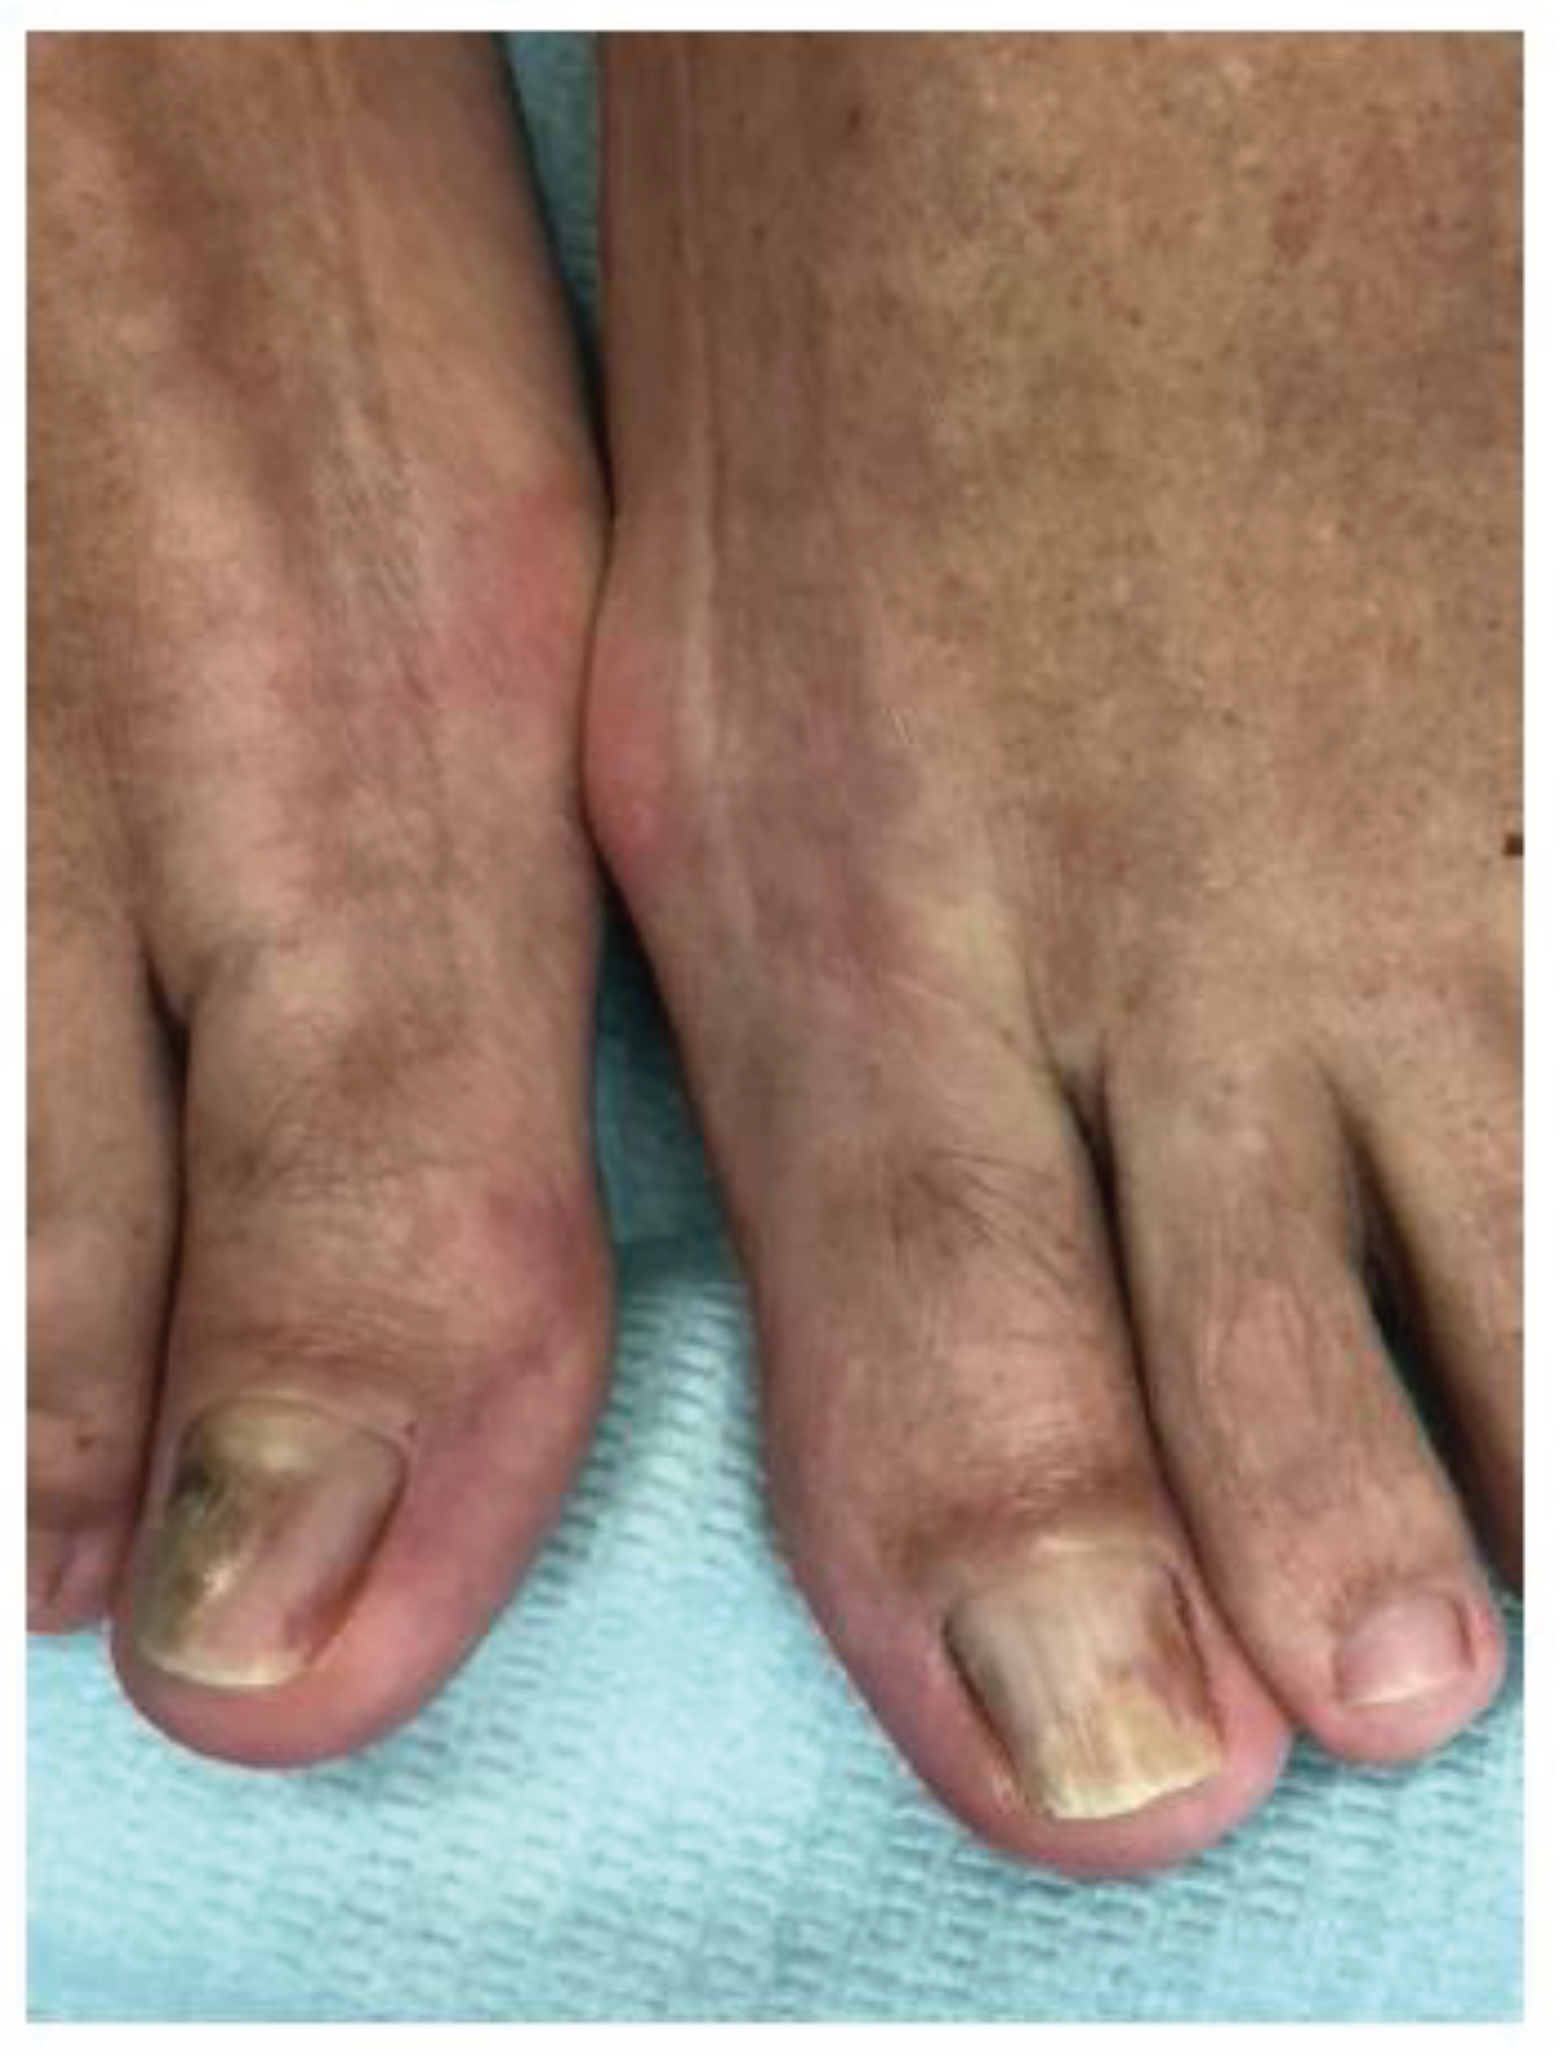

- Roberts DT, Evans EG. Subungual dermatophytoma complicating dermatophyte onychomycosis. Br J Dermatol. 1998;138(1):189-90. [CrossRef]

- Burkhart CN, Burkhart CG, Gupta AK. Dermatophytoma: Recalcitrance to treatment because of existence of fungal biofilm. J Am Acad Dermatol. 2002 Oct;47(4):629-31. [CrossRef]

- Markantonatou AM, Samaras K, Vyzantiadis TA. Dermatophytic biofilms: Characteristics, significance and treatment approaches. J Fungi (Basel). 2023;9(2):228. [CrossRef]